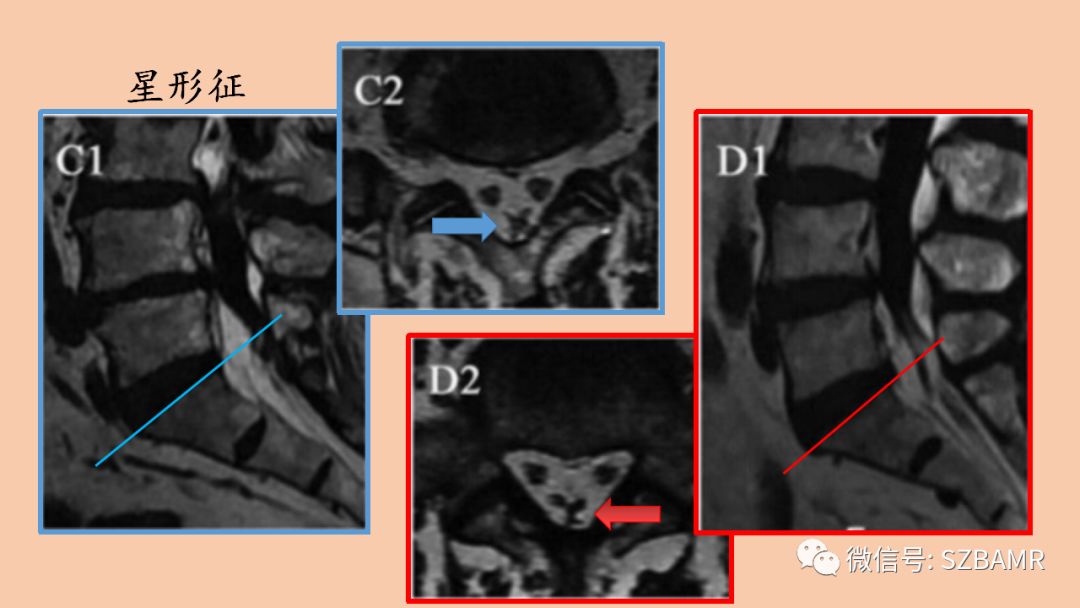

影像表现:胸椎通常堆积于椎管后方,腰椎包绕整个硬膜囊的脂肪信号,压迫硬膜囊,横断面上出现“Y字征”、“星形征”、“线征”或“椭圆征”。